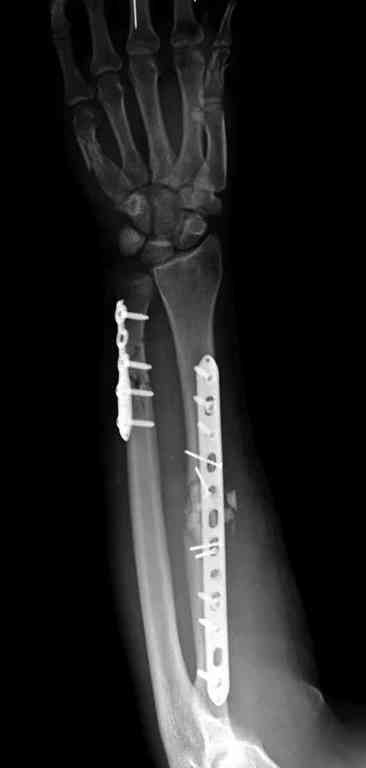

Отечность в зоне фиксации является противопоказанием к открытому методу. Для профилактики осложнений с фиксацией можно повременить применением стабилизирующего наружного фиксатора. Фиксатор восстанавливает длину конечности, облегчает в будущем репозицию и создает благоприятные условии для спадения отека. Также позволяет экономить средства, вместо дорогого стационара больной может находится на амбулаторном наблюдении. Появление симптома "skin wrinkle test" (морщинки) подскажет о готовности кожного покрова для окончательной операции на костях.

Множественная огнестрельная травма конечностей, перелом костей предплечья, фиксация в первые часы и дефект мягких тканей, мероприятия по закрытию...